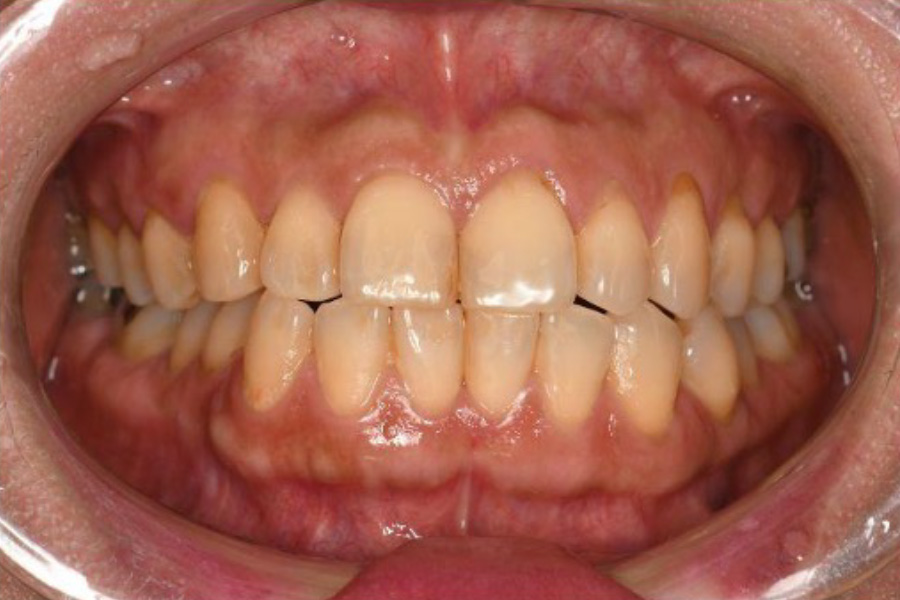

治療前

治療後

| 治療内容 | 全顎治療:歯周病治療、根管治療、 歯肉弁剥離掻爬術(フラップ手術)、 セラミック治療、ダイレクトボンディング |